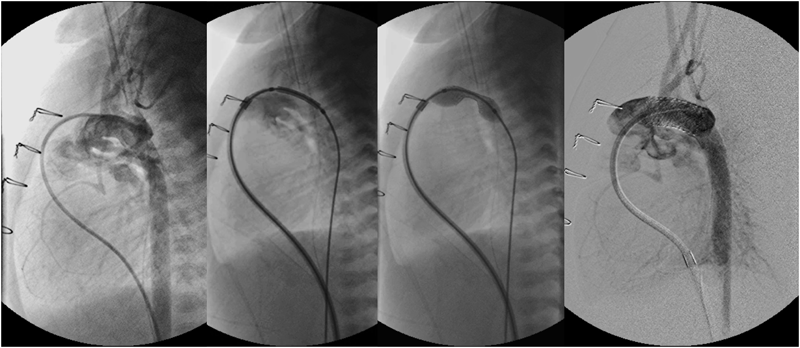

房室弁の損傷をきたす可能性があるので必ず正面・側面透視を使用する.右房(RA)内にあるカテーテルを後左方へ向けて左房(LA)へ通す.軽くテストインフレーションして心室に引き込まれないことを確認してから,力まずにスピードを付けてシャフトを手前に短く引く(B).抵抗を感じるが直ぐに下大静脈(IVC)へ入り込むので(C),RAへ押し戻す(D).小さめ(1 ccの注入)から開始し,徐々にサイズアップするのが安全である.

現在日本でBASに保険適応されているカテーテルは2種類ある.Rashkind catheterは最大注入量が2 cc,最大径が14 mm,適合シースは6Fである.一方Miller catheterは最大注入量が4 cc,最大径が19 mmと大きいが,適合シースは7Fである.できる限り大腿静脈(FV)の閉塞を避けるためにRashkind catheterが選択されることが多い.低体重児の場合はさらにFVが細いので,BASには保険適応がないが,4F,5Fのシースで使用できる血栓除去用のFogaty catheterが有用である(Table 2).新生児期にBASが必要となる疾患としては,心房間mixingが必要な完全大血管転位(TGA)・両大血管右室起始(DORV),生存に心房間左右短絡が必要な左心低形成症候群(HLHS)・重症大動脈弁狭窄(cAS),反対に右左短絡が必要な三尖弁閉鎖(TA)・心室中隔欠損を伴わない肺動脈閉鎖(PA IVS)などがある.